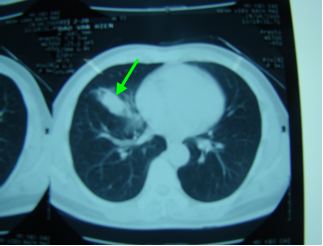

Chụp cắt lớp vi tính lồng ngực: Khối u thuỳ giữa phổi phải kích thước 26 ´ 13mm, không có hạch rốn phổi, trung thất.

Chụp cắt lớp vi tính lồng ngực

Trước điều trị: Hình ảnh khối u thuỳ phổi phải, kích thước 26x13mm

Sau điều trị: Không còn khối u, không có hạch trung thất